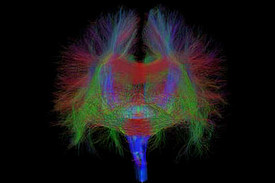

Bei bestimmten Bewegungsstörungen, die nicht oder nicht mehr ausreichend auf eine medikamentöse Therapie ansprechen, ist es möglich, die hierfür verantwortlichen Hirnareale durch die sog. Tiefe Hirnstimulation zu beeinflussen. Hierbei werden feine Elektroden in das Gehirn eingesetzt, um fehlerhafte Nervenstrukturen mit elektrischen Impulsen zu aktivieren oder zu hemmen. Beim Morbus Parkinson, dem essentiellen Tremor oder der Dystonie sind beispielsweise spezifische Hirnareale überaktiv, die dann gezielt durch die Tiefe Hirnstimulation gehemmt und die Symptome wie Zittern oder Muskelsteifigkeit dadurch unterdrückt werden können. Die Hirnregionen selbst bleiben dabei intakt, sodass die Stimulation jederzeit rückgängig gemacht werden kann. Die elektrische Stimulation wird durch einen Impulsgeber gesteuert, der ähnlich wie ein Herzschrittmacher unter die Haut an der Brust der Patient:innen implantiert wird. Die Einstellungen des Impulsgebers lassen sich von außen jederzeit verstellen, sodass die Stimulation an veränderte Bedürfnisse der Patient:innen stets angepasst werden kann.

Neben den Bewegungsstörungen sind mittlerweile auch einige neuropsychiatrische Erkrankungen, wie die Depression oder Zwangsstörungen bekannt, bei denen fehlerhafte Hirnareale durch die Tiefe Hirnstimulation verändert (=moduliert) werden können. Bei schweren therapieresistenten Verläufen kann auch hier dieses Verfahren angeboten werden.

Tiefe Hirnstimulation bei psychiatrischen Erkrankungen

Neben den Bewegungsstörungen sind mittlerweile auch einige neuropsychiatrische Erkrankungen, wie die Depression oder Zwangsstörungen bekannt, bei denen fehlerhafte Hirnareale durch die Tiefe Hirnstimulation verändert (=moduliert) werden können. Gemeinsam mit dem ZI Mannheim erforschen wir neue Zielstrukturen und Indikationen.